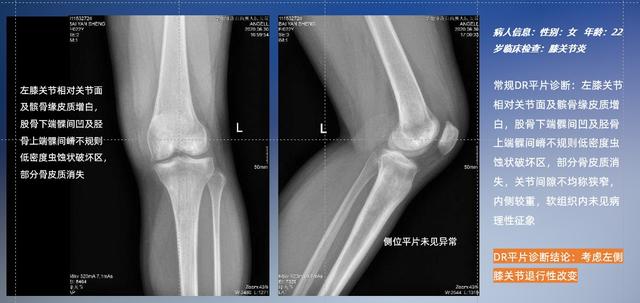

以膝關節疾病檢查為例,膝關節在解剖學意義上是一種較為復雜的最大關節,由脛骨上端、股骨下端及髕骨組成。在股骨與脛骨的關節面之間存在兩塊半月板,分別處于內側、外側。膝關節的運動主要為伸、屈,在半屈位時可進行小幅度的旋外、旋內運動。隨著現代人們體育生活以及肥胖的增加,膝關節疾病出現高發趨勢,特別是關節磨損、膝關節炎與骨關節炎等關節退行性改變,長時間的內翻負荷會造成內側關節軟骨、骨性關節面的磨損。目前針對此類疾病的檢查主要為平片下的負重位檢查、CT檢查以及MRI檢查,相較于非負重位檢查,負重位檢查能更加真實反映膝關節結構中脛骨、股骨、髕骨實際對位關系和關節面的形態特征及關節間隙大小,對膝關節骨關節病診斷準確率高。

普通平片掃描與WR-3D掃描前后診斷結果對比

與此同時,數字化X線攝影技術相較于CTMRI來說,能快速獲取真實、直觀、滿足臨床需要的影像。DR的圖像具有圖像層次豐富、空間分辨力高、影像邊緣銳利清晰、密度分辨力高級細微結構表現出色等特點,針對膝關節解剖結構數字化X線攝影技術應用價值很高,尤其是是對骨小梁與骨皮質的顯示非常清楚。在負重位狀態下,數字化X線三維攝影掃描與重建,能夠更好的呈現受檢者關節受力改變的狀態。安健科技創新的WR-3D動態三維數字化X線攝影技術,通過數字化X線攝影完成三維掃描并重建三維影像信息,包括MPR多平面重建、MIP重建以及VR繪制。掃描時間短,劑量相較于CT設備大幅縮減,同時成本更低,在臨床診斷以及醫療方案制定中具有極大的價值意義。相較于普通平片下的負重位掃描,負重位動態三維掃描攝影技術能夠避免二維狀態下的組織結構重疊、密度分辨率不足、組織解剖結構難以分辨等問題,WR-3D支持多角度的動態三維攝影觀察,能全面的呈現被檢查部位在多個角度下三維影像信息,極大的減少了二維負重位檢查的漏診率。